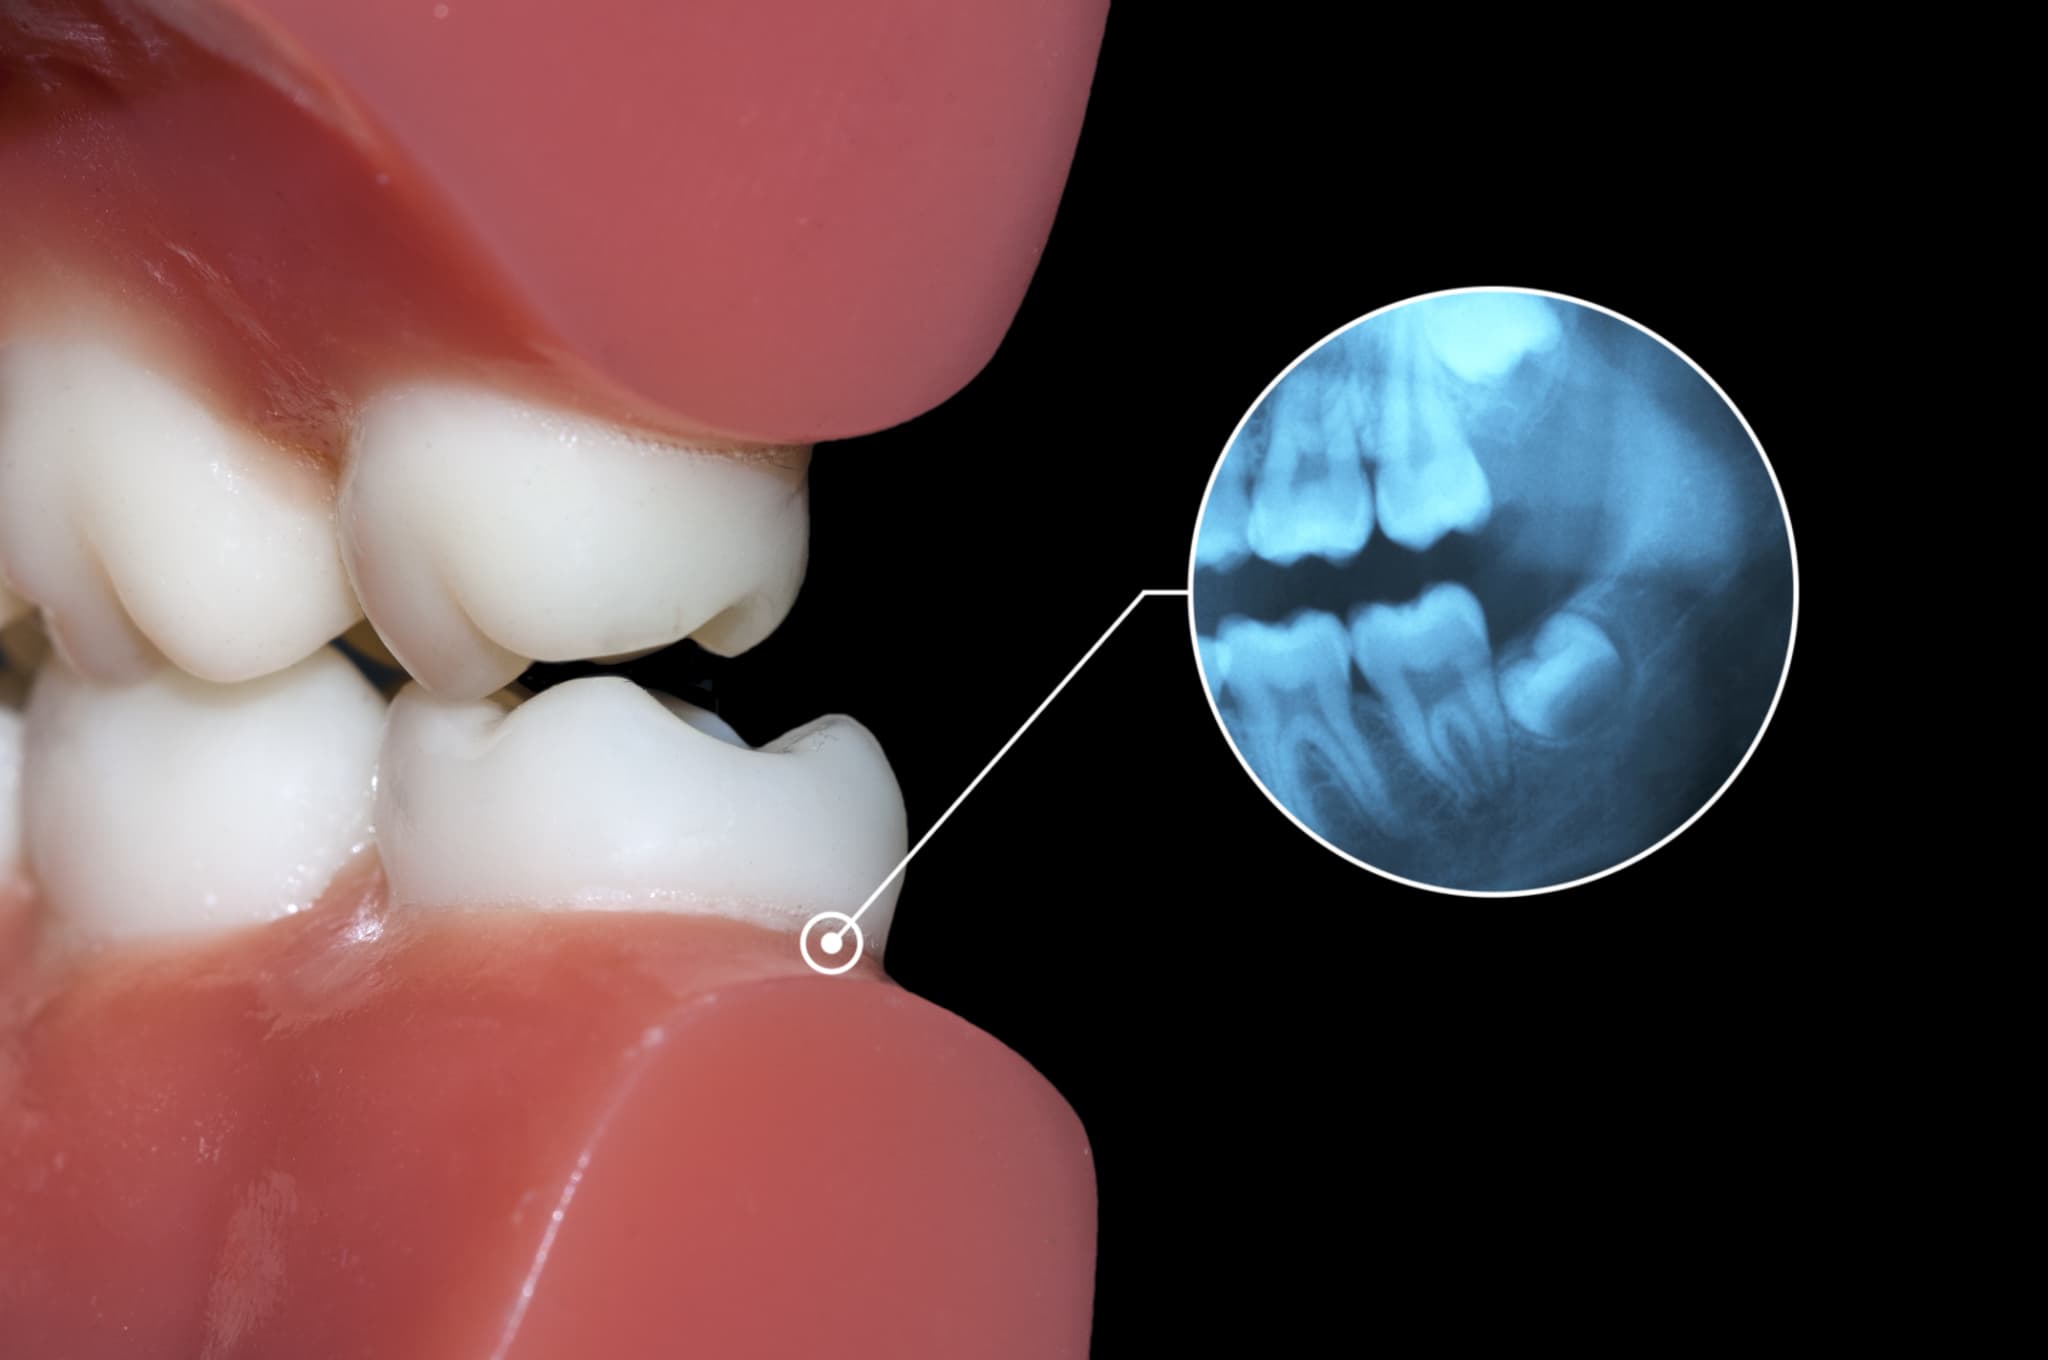

手前の歯が虫歯になるリスクが高まる

親知らずが一部だけ歯ぐきから出ている場合や、一部が埋まっている場合は、手前の歯との間に汚れが溜まりやすくなります。この部分に汚れが残ったままになると細菌が増え、虫歯が発生しやすくなります。

問題となるのは、親知らずだけでなく手前の歯に虫歯ができる可能性がある点です。奥歯は見えにくく清掃も難しいため、虫歯が進行してから気づくケースもあります。

診察・レントゲン検査

まず歯科医院での診察と検査から始まります。目視だけでは歯の全体像を正確に把握できないため、レントゲンやCT検査で親知らずの位置、角度、神経との距離、骨の状態などを詳しく確認します。